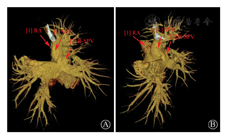

右上肺静脉引流至上腔静脉入右心房口部后壁(为更好显示肺静脉异位引流,重建时未采用标准体位)